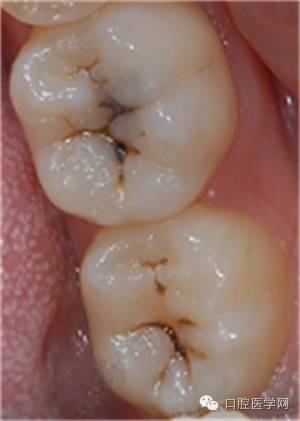

Z350树脂制作印章

要点

1、有效隔湿,棉卷或橡皮障

2 、轻吹牙面

3 、印章应覆盖所有需恢复形态的牙面

4、 印章需要有一定的厚度,否者易变性或取出时折裂。

固化 光照时间要够,充分固化

印章完成用探针将印章取下,接触面涂布凡士林,若菲边较多,可作适当修整